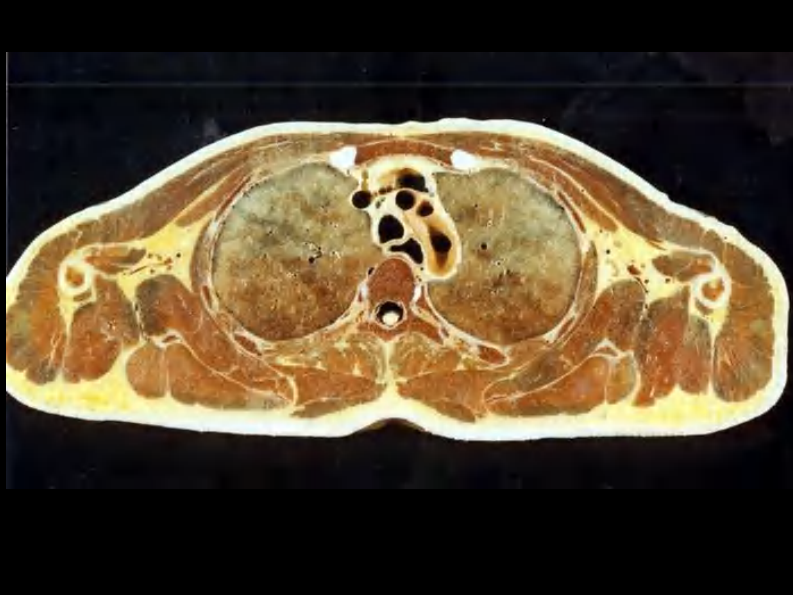

07 纵隔连续横断层解剖及CT.pdf